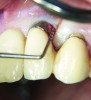

Following active therapy, probing depths of 4 mm or less (Figure 1 and Figure 2) and the absence of bleeding on probing contribute to improved health and stability. Increasing probing depths should alert the therapist to identify etiology and determine whether active periodontal therapy is warranted. The absence of bleeding on probing is a strong predictor of stability, and although the presence of bleeding does not always result in attachment loss, it remains an important parameter to evaluate.14 Bleeding on probing is also an important parameter for assessing implant health during maintenance. Serino et al15 evaluated 27 patients with 19 dental implants over 5 years. Patients were seen every 6 months and they concluded that bleeding on probing was a good predictor for attachment loss and disease progression around the implants (Figure 3).

Fig 1. A deep pocket of 7 mm prior to active periodontal therapy.

Figure 1

Fig 2. Following periodontal regenerative therapy, the tooth with a 3-mm probing depth, which facilitates maintenance.

Figure 2